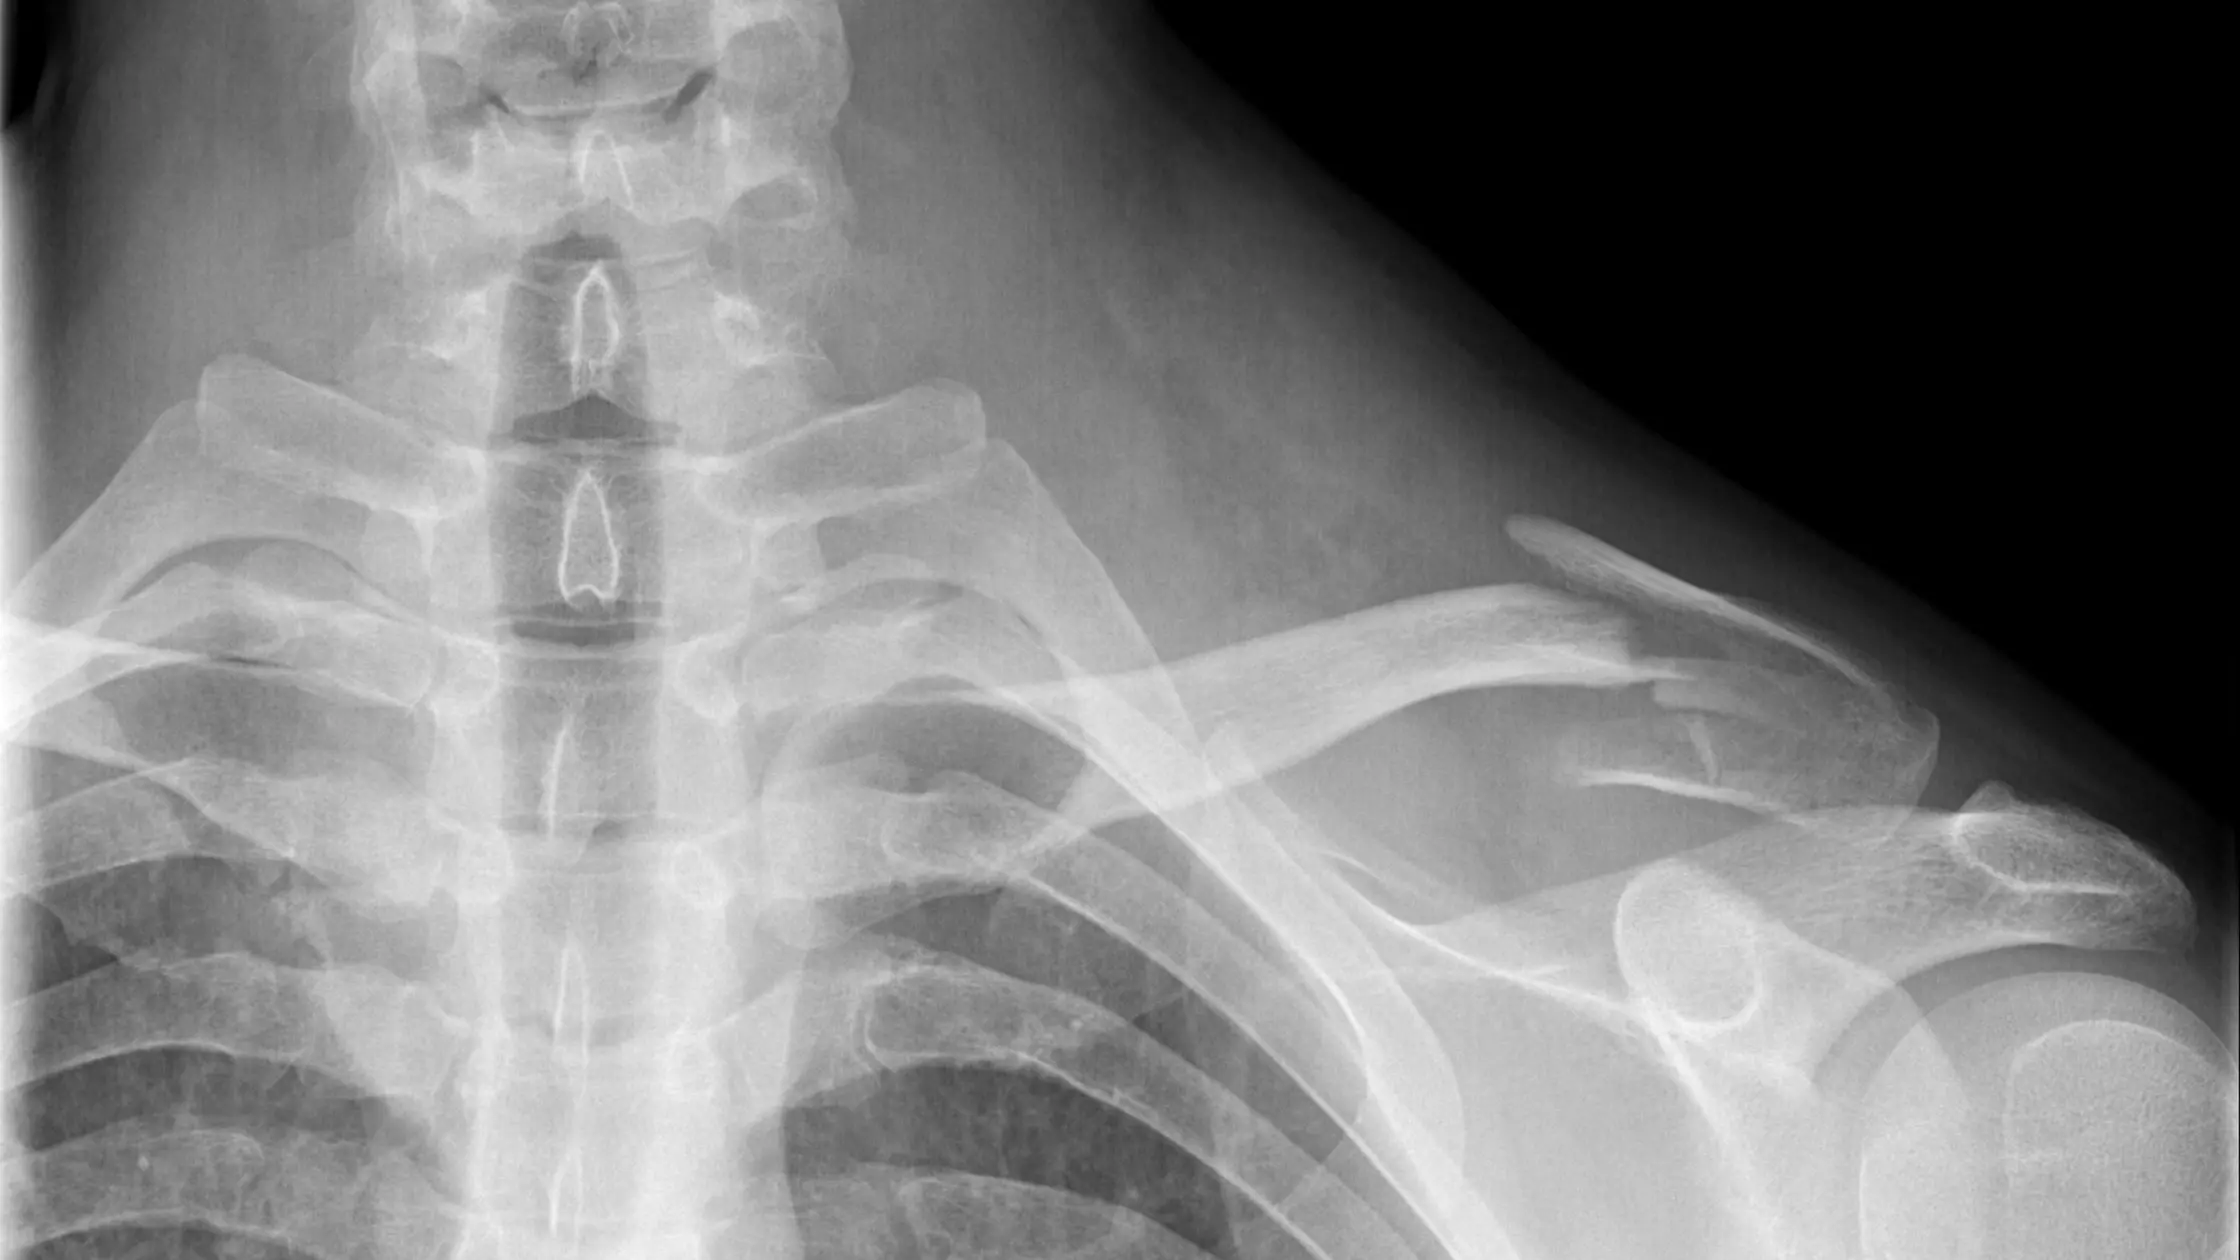

Você pode suspeitar de uma fratura se sentir Dor no Braço, inchaço ou incapacidade de mover o cotovelo ou ombro. O Diagnóstico de Fratura geralmente é confirmado com raios-X ou, em alguns casos, com uma tomografia computadorizada.

As opções de Tratamento do Úmero variam de imobilização com talas ou gesso até a Cirurgia do Braço, dependendo da localização e da gravidade da fratura. A cirurgia pode envolver a colocação de placas, parafusos ou hastes intramedulares.